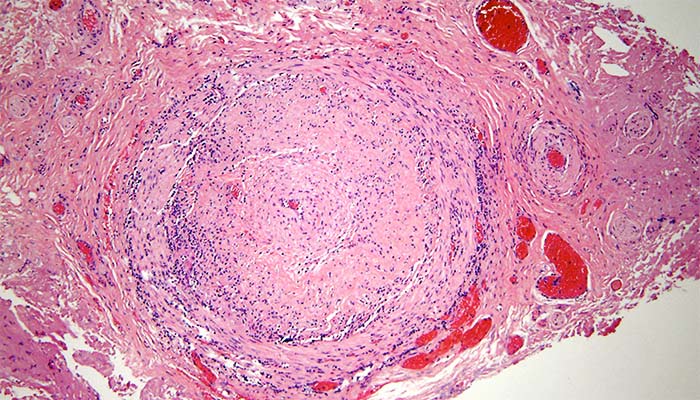

Magnified view of a cross section through the temporal artery obtained from a biopsy. The artery is completely clogged with inflammation due to giant cell arteritis.